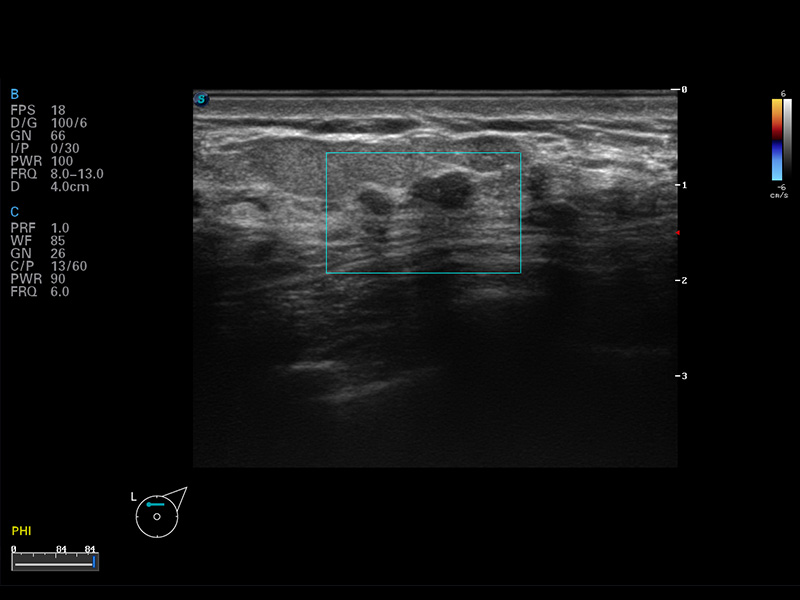

S8 EXP便携式彩色多普勒超声诊断仪是九州酷游研发的高端全身应用型便携彩超。高通道的VIS平台融合可视化(Visual)、智能化(Intelligent)和人性化(Smart)的特点,配以九州酷游自主研发生产的探头大家族,使您能够快速、准确的获得病人信息,提高工作效率的同时减轻疲劳。

空间复合成像